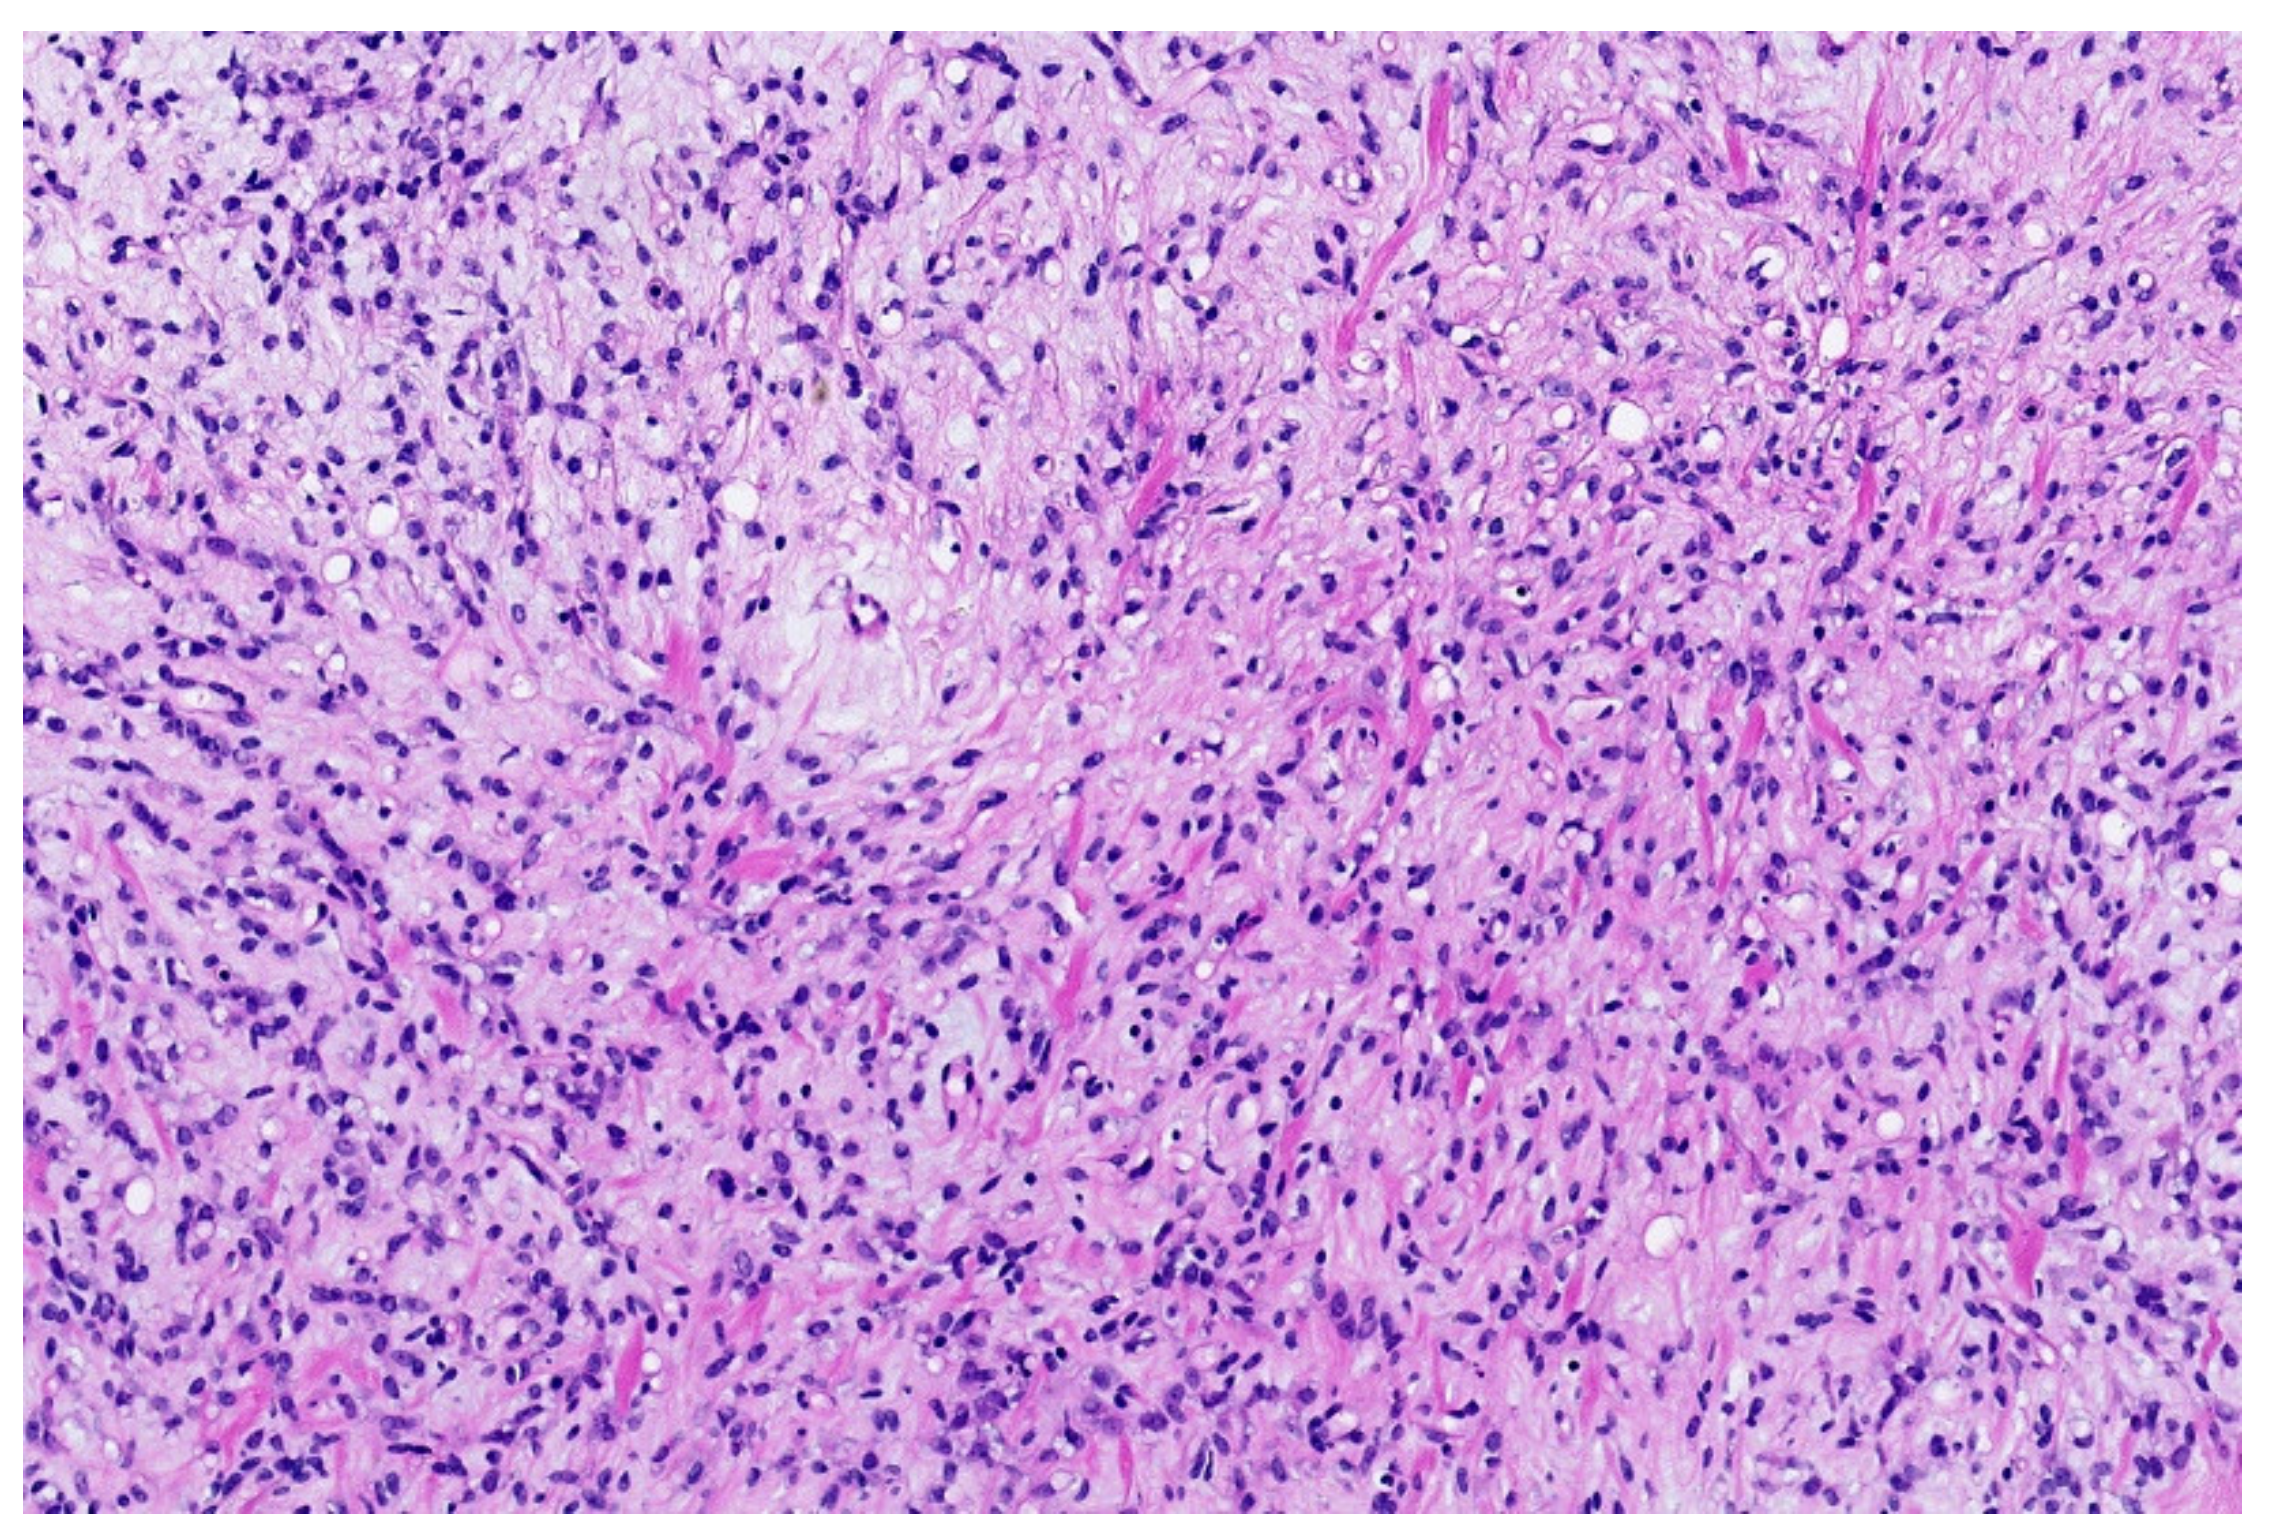

4. Myxoid Liposarcoma (MLS)